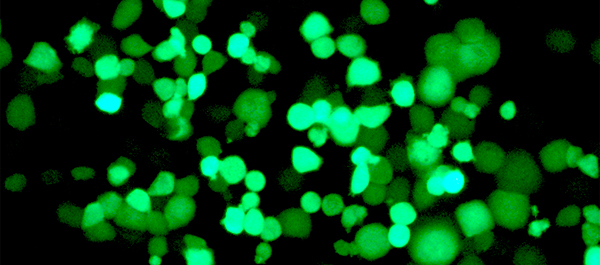

Células tumorales infectadas por el virus (fluorescente) cinco días después de la infección. (Imagen: IDIBAPS-IRB Barcelona)

Los virus oncoselectivos que se crearon eran muy sofisticados, pues se activaban por CPEB4 pero se reprimían por CPEB1. Así, los investigadores lograron una actividad viral atenuada en células normales, mientras que en las tumorales se mantuvo o, incluso, aumentó la potencia de los virus. "Cuando los virus modificados entraban en las células tumorales, replicaban su genoma y, al salir, destruían la célula liberando más partículas del virus, capaces de infectar, a su vez, a más células cancerígenas", explica Fillat, que añade que "esta nueva aproximación es muy interesante ya que se trata de una terapia que se amplifica de forma selectiva en el propio tumor".